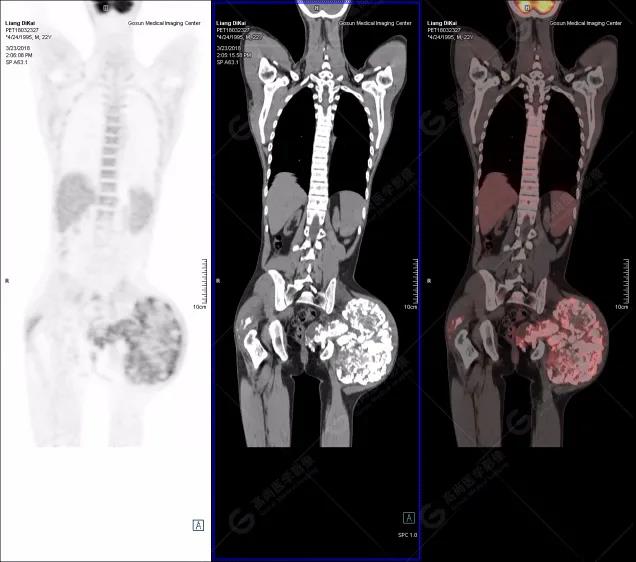

本中心PET/CT提示

1.右肘關(guān)節(jié)周圍、骶尾部皮下、雙側(cè)臀部、盆腔左側(cè)壁及左側(cè)大腿根部肌肉、肌間隙多發(fā)結(jié)節(jié)狀、片塊狀及不規(guī)則巨塊狀高密度鈣化灶,伴代謝不均勻輕度增高,考慮為鈣質(zhì)沉著癥;

2.甲狀腺雙葉后方多發(fā)(右2個,左1個)小結(jié)節(jié)狀軟組織影,部分代謝輕度增高,多考慮為甲狀旁腺腺瘤。

患者行甲狀腺雙葉后方結(jié)節(jié)切除,術(shù)后病理甲狀旁腺腺瘤;病灶切除后,全身多發(fā)腫塊逐漸消失。